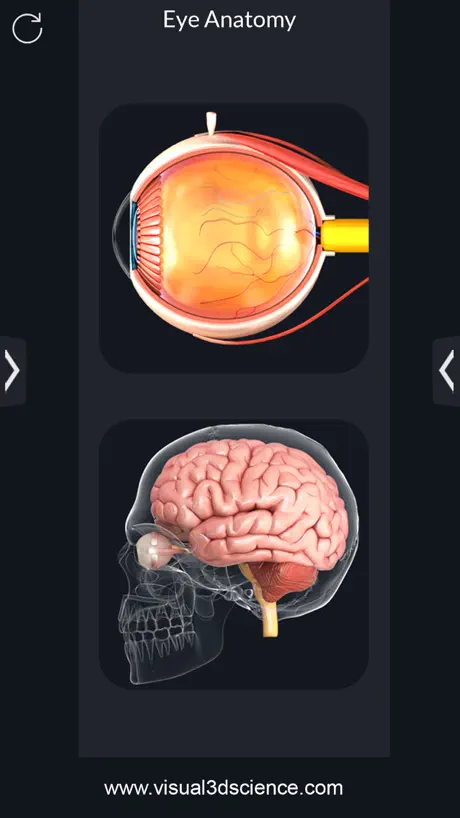

Screenshots